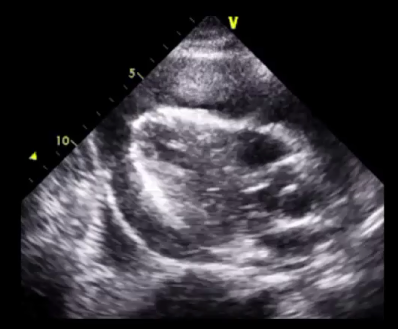

Curso de ecografía crítica en todas sus modalidades (ecocardiografía transtorácica y transesofágica, ecografía pulmonar, vascular, cerebral, FAST) dirigido a: médicos intensivistas, emergenciólogos, anestesiólogos, internistas, médicos de familia, neumólogos, cardiólogos y a todo aquel interesado por utilizar la ecografía como parte del examen físico del paciente crítico.

Para estimar los parámetros hemodinámicos de forma no invasiva que obtenemos por métodos más invasivos no exentos de posibles complicaciones inherentes a su colocación, a pie de cama del paciente tales como: PCP, gasto cardíaco, variabilidad del volumen sistólico, PVC, resistencias vasculares sistémicas y pulmonares, agua extravascular pulmonar y guiar las terapéuticas administradas.

En nuestro afán por seguir el trabajo empezado hace ya varios años desde Europa (España) por impulsar la ecografía crítica para intensivistas, emergenciólogos, anestesistas, internistas, subespecialistas de obstetricia crítica, neumólogos y todo aquel médico interesado en aprender a utilizar la ecografía como parte de su examen físico, ahora desde Centroamérica (Panamá), hemos escrito el primer libro Latinoamericano-Europeo de ecografía crítica sub-especializado y dedicado exclusivamente al paciente con shock de cualquier etiología (obstructivo, distributivo, cardiogénico, hipovolémico) que involucra todas las modalidades ecográficas: ecocardiografía, ecografía pulmonar, vascular, abdominal, del sistema nervioso central/doppler transcraneal, etc) en el que participan muchos expertos en sus respectivas áreas tanto de Europa como de América y también algunos profesores del EDEC (Diploma Europeo de ecocardiografía / ESCIM- Sociedad Europea de Medicina intensiva).